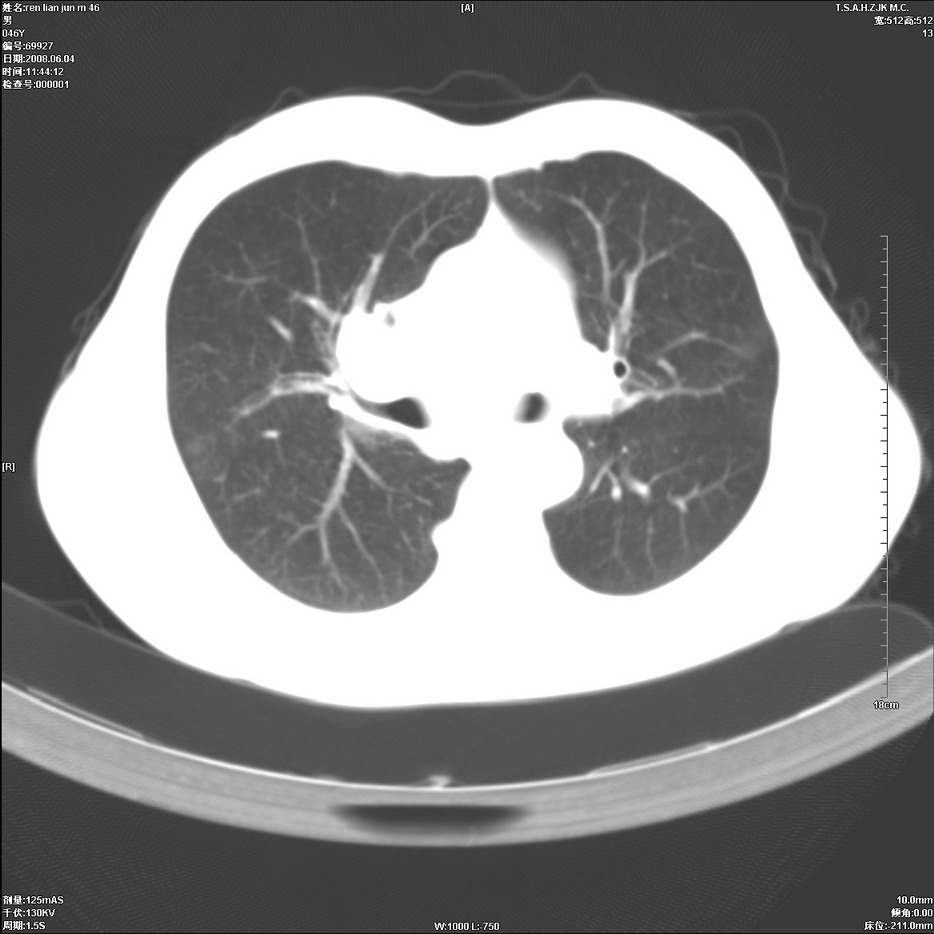

以下是引用qiu999在2008-6-5 17:14:00的发言:[br]考虑右肺中心型肺癌.颅内应做增强检查.

以下是引用形影不离在2008-6-5 19:18:00的发言:[br]右肺中心型肺癌并纵隔及左侧腋窝淋巴结转移,颅内应做增强检查。

以下是引用杀毒软件在2008-6-5 18:33:00的发言:[br]支持考虑右肺中心型肺癌,颅内病变是不是转移,不好说